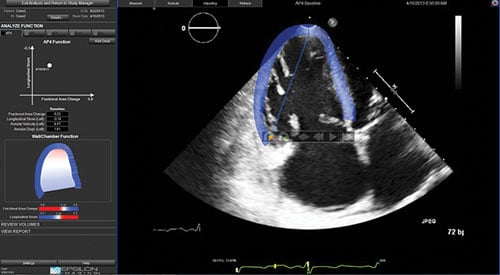

Cardiac imaging surveillance of cancer patients can be done using echocardiography, nuclear imaging or magnetic resonance imaging (MRI), said Storozynsky. However, echo is the easiest modality for most patients and centers to access, and is less expensive than nuclear or MRI. He said 3-D echo allows the calculation of very accurate ejection fractions. Live tissue Doppler allows imaging of cardiac function by assessing wall motion, and this can be enhanced using echo contrast.

One cardiac ultrasound innovation that is widely used to assess cancer patients’ hearts is echo strain imaging. This advanced visualization software allows simultaneous assessment of three different views of the myocardium. The software allows quantification of the amount of left ventricular (LV) systolic function muscle strain in each view. Storozynsky said strain imaging can show microscopic changes in movement of the myocardium prior to the presentation of symptoms.